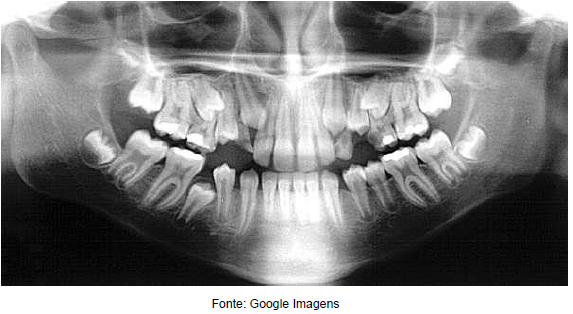

Observe a imagem abaixo mostra uma radiografia revelada através de um sistema digital. Assinale

qual o tipo de radiografia representada.